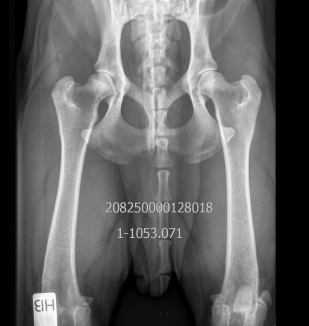

HD: A/A